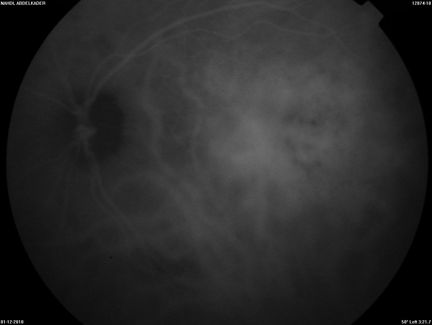

The patient refused to be treated with radiotherapy due the risk of complications of such treatment and he received systemic chemotherapy every three weeks for six cycles, (epirubicin 100 mg/m2, cyclophosphamide 500 mg/m2, 5-fluorouracil 500 mg/m2). Five months into treatment, the patient reported a decrease in symptoms, his BCVA improved to 6/10 and the choroidal lesion showed complete regression on both MRI and fundoscopy (Figures 5, 6, 7).

Figure 5: Dilated fundus examination of the right eye after one cycle of chemotherapy showing the beginning of chorioretinal atrophy.

Figure 6: Dilated fundus examination of the right eye after treatment (six cycles of chemotherapy) showing a large area of chrorioretinal atrophy of the posterior pole and the upper temporal arcade without serous macular detachment, and normal papilla.